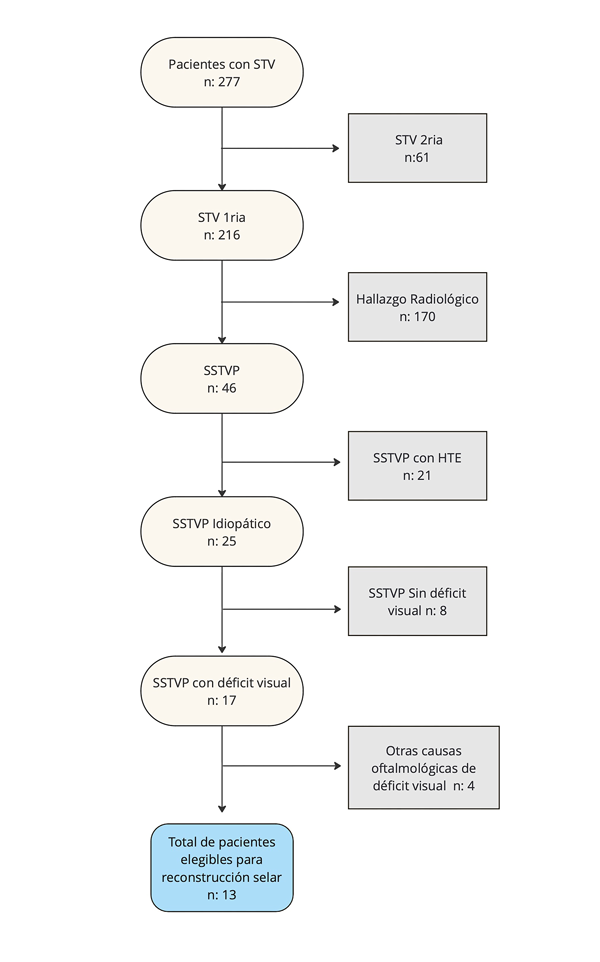

De los pacientes que se presentaron con STV (N: 277) se realizó una selección muy estricta (Figura 3). En una primera instancia, se distinguió entre pacientes con STV primaria y secundaria. Se consideró STV secundaria a quienes presentaron antecedentes de algún tipo de tratamiento quirúrgico, farmacológico o radioterapia de su patología selar. Se excluyeron a los pacientes con STV secundaria (n: 61).

Figura 3. Diagrama de flujo de pacientes. HTE: Hipertensión endocraneana. SSTVP: Síndrome de silla turca vacía primaria. STV: Silla turca vacía.

En una segunda instancia, de los pacientes con STV primaria se identificaron a los sintomáticos y a los no sintomáticos. Se excluyeron a los que se consideraron hallazgos radiológicos (n: 170). A los pacientes sintomáticos se los denominó como SSTVP (n: 46).

En una tercera instancia, los pacientes con SSTVP (n: 46) se tamizaron en dos grupos según presentaron (n: 21) o no (n: 25) hipertensión endocraneana (HTE). Para esto, se realizó un interrogatorio de rutina dirigido, un fondo de ojo con lámpara de hendidura, una RM con protocolo específico y una punción lumbar con manometría. Se excluyeron a los que presentaron HTE (por ejemplo, SSTVP asociado a malformación de Chiari tipo 1, hidrocefalia, alteración de circulación del líquido cefalorraquídeo, tumor, pseudotumor cerebri, patología fúngica, entre otros). Estos últimos fueron candidatos a otros tipos de cirugías, específicas para su causa.

En una cuarta etapa, quedaron tamizados los pacientes con SSTVP idiopáticos (n: 25). De estos pacientes se seleccionaron a quienes presentaron un déficit visual (n: 17). Para evidenciarlo se realizó una campimetría computarizada. Se excluyeron a quienes no presentaron déficit visual (n: 8).

En una quinta etapa, los pacientes con SSTVP idiopática con déficit visual (n: 17) fueron enviados para un estudio exhaustivo oftalmológico. Esto a fines de descartar otras causas de déficit visual frecuentes en nuestro medio (por ejemplo, retinopatía diabética, retinopatía hipertensiva). Se excluyeron a aquellos en quienes el oftalmólogo atribuyó el déficit a otra causa (n: 4).

En una sexta etapa, se indicó reconstrucción endoscópica del piso selar con técnica de 7E a los pacientes que cumplieron con nuestro estricto protocolo de selección (N: 13).